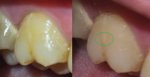

Аноним OP 20/08/24 Втр 16:01:13 #34 №1563530

Был у ортодонта-челюстного-ортопеда. Сказала что каппу без передних зубов опасно дольше 2 недель носить и зубы передние начнут вылезать вниз и прикус испортится ещё больше. Сказала нужно удалить нижние два зуба мудрости т.к. в них она увидела белые пятна рядом - признак воспаления...А вдруг это ваще всё с самого начала из-за них? Хотя боли чаще именно в верхней части челюсти, а нижня никада не болит...И почему другие врачи на это воспаление не указали?...Ну и рентген старый, ему год уже..

Аноним 20/08/24 Втр 16:07:52 #35 №1563535

>>1563530

>белые пятна рядом

Черные пятна* фикс

image.png

Хотя ИИ грит это не воспаление а из-за ретинированности зубов...